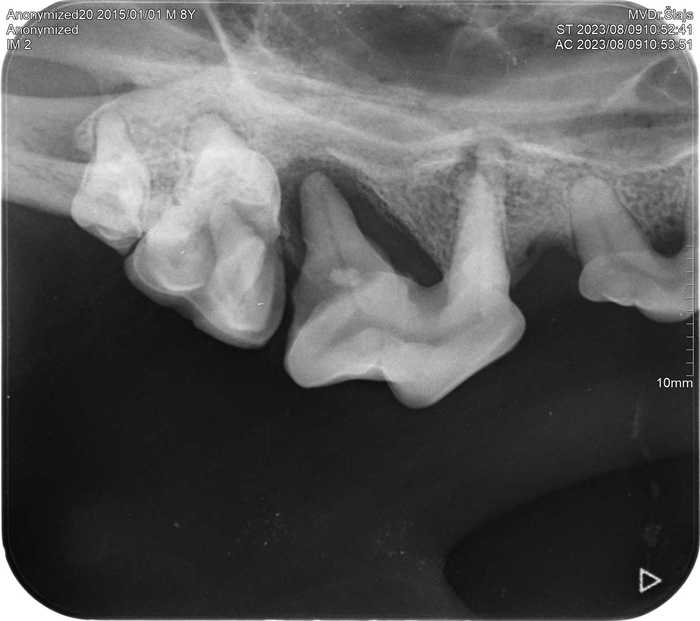

Již nyní má na našem pracovišti RTG vyšetření nezastupitelné místo během vyšetření zubů a dutiny ústní u králíků, morčat, psů i koček.

Zubní intraorální RTG nám umožňuje přesnější diagnostiku onemocnění zubů, díky čemuž je úspěšnější i léčba.

S pomocí intraorálního RTG s vysokým rozlišením jsme schopni ještě před vlastním zubařským zákrokem přesně stanovit diagnózu a rozhodnout, zda a kde přesně provést chirurgický zákrok.

Díky posouzení zubních kořenů a stavu kostního podkladu zubů můžeme provést zákrok přesně v místě, kde je potřeba a stanovit následnou léčbu tak, aby hojení probíhalo co nejrychleji a pacient nemusel zbytečně podstupovat opakované ošetření.